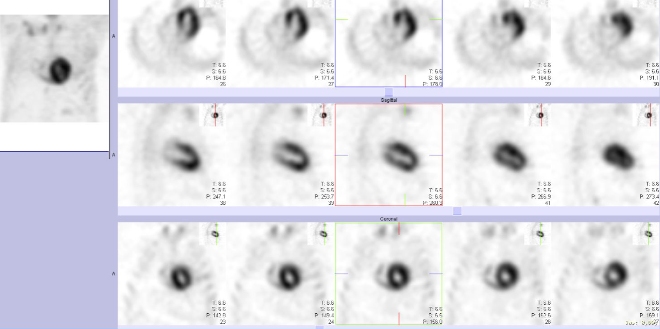

/ Obr. č. 2: Tomografická scintigrafie myokardu. /

Na planárních scintigramech a na tomografických řezech prokazujeme výrazně patologicky zvýšenou koncentraci radiofarmaka v myokardu levé srdeční komory.

Stupeň akumulace dle vizuálního skóre - Grade 3.

Závěr: Nález svědčí pro patologicky zvýšenou akumulaci radiofarmaka v myokardu.

Nález potvrzuje transthyretinovou srdeční amyloidózu.